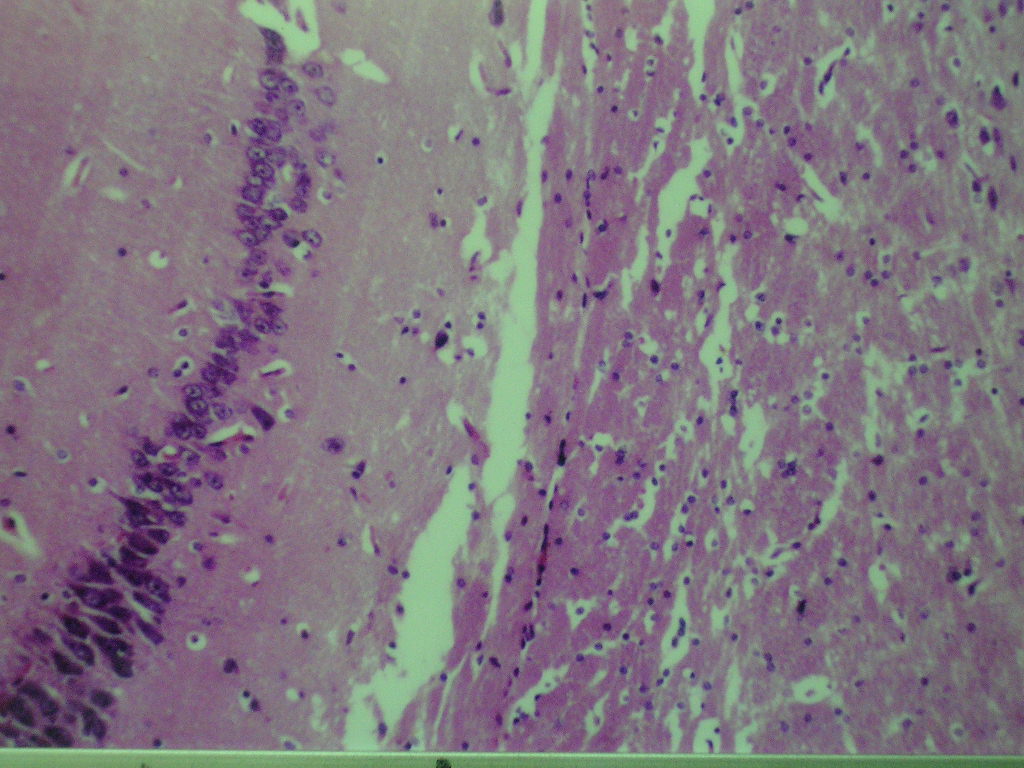

Fig (1): Micrograph of brain section of normal control rat showing normal morphological structure of the hippocampus (H& E X40). Fig (2): Micrograph of brain section of ovariectomized control rats showing normal morphological structure of the hippocampus (H& E X 40). Fig (3): Micrograph of brain section of Al-intoxicated ovariectomized (AD group) rats showing various sizes of amyloid plaques formation (arrow) in the cerebral cortex and hippocampus (H& E X 40). Fig (4): Micrograph of brain section of AD rats treated with α-chymotrypcin in a dose of (8.1 unit/rat/day) showed the presence of focal gliosis in the cerebrum and disappearance of most of amyloid plaques.

Fig. 3: Micrograph of brain section of Al-intoxicated ovariectomized (AD group) rat showing various sizes of amyloid plaques formation (arrow) in the cerebral cortex and hippocampus (H& E X 40).